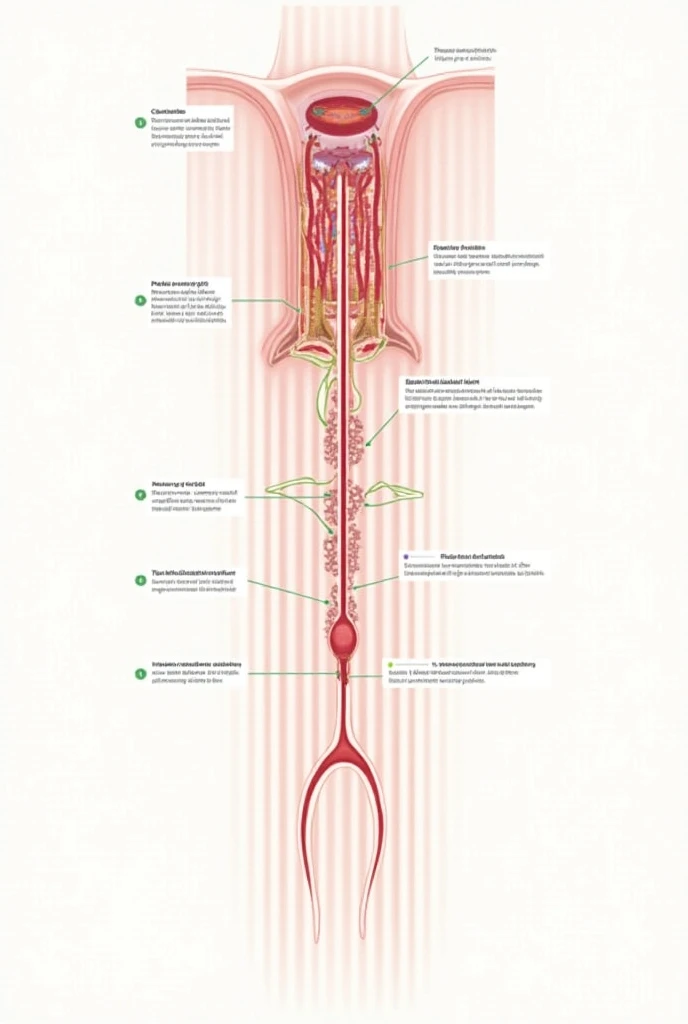

Realice un dibujo de la piel. Coloque las siguientes referencias: Epidermis Fermis Hypodermis Keratinized squamous stratified epithelium Hair Sebaceous gland Sweat gland Pilo erector muscle Connective tissue Blood vessels Nerves Adipocytes

Epidermis Fermis Hypodermis Keratinized squamous stratified epithelium Hair Sebaceous gland Sweat gland Pilo erector muscle Connective tissue Blood vessels Nerves Adipocytes